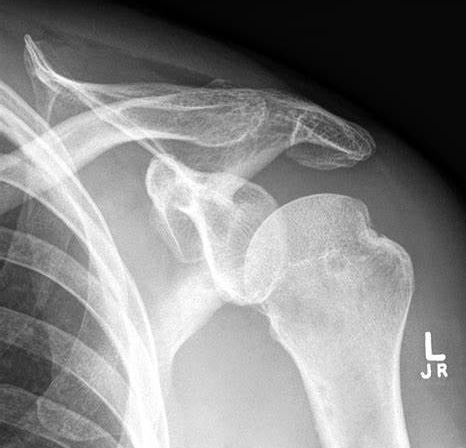

What do these X-rays show?